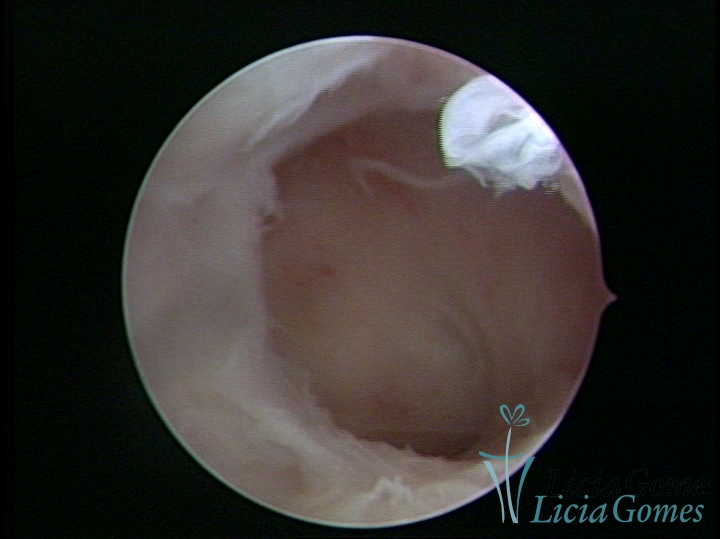

• SINÉQUIA TIPO FIBROMUSCULAR